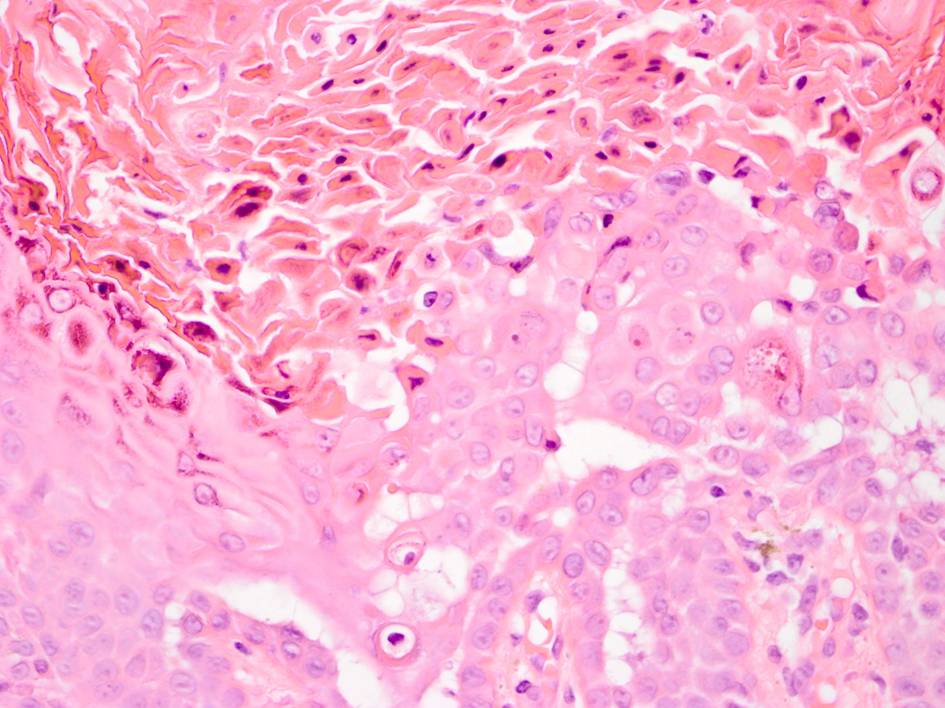

reactie. Bij dyskeratose zijn er 2 klassieke histologische kenmerken te zien:

corps ronde en

grains.

Corps

ronde: dyskeratotische acantholytische keratinocyt met cytoplasmatische opheldering

gelegen in het stratum granulosum. Te herkennen aan hun ronde vorm. In het cytoplasma

van corps ronds ziet men grote, ronde, homogene dyskeratotische vormsels, vaak

rondom gedegenereerde kernen, omgeven door een heldere zone.

Grains:

dyskeratotische keratinocyt gelegen in het stratum corneum. Te herkennen als

eosinofiel aankleurende afgeplatte cellen met een homogeen donkere kern die

de vorm heeft van een graankorrel. Grains lijken op parakeratotische cellen

maar zijn wat groter.

| corps ronde

en grains als kenmerk van dyskeratose |